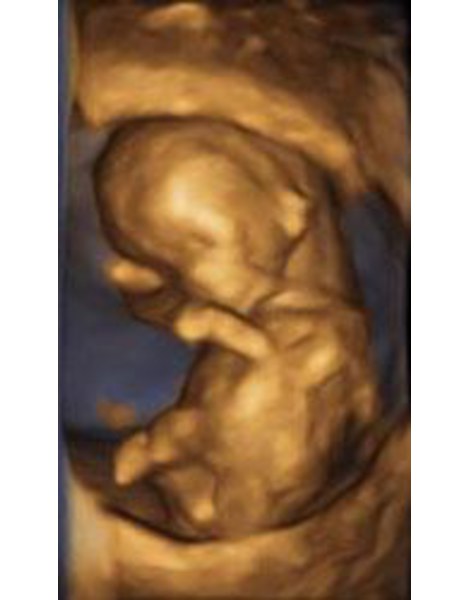

FA Frauenheilkunde und Geburtshilfe

Fotos und Videos